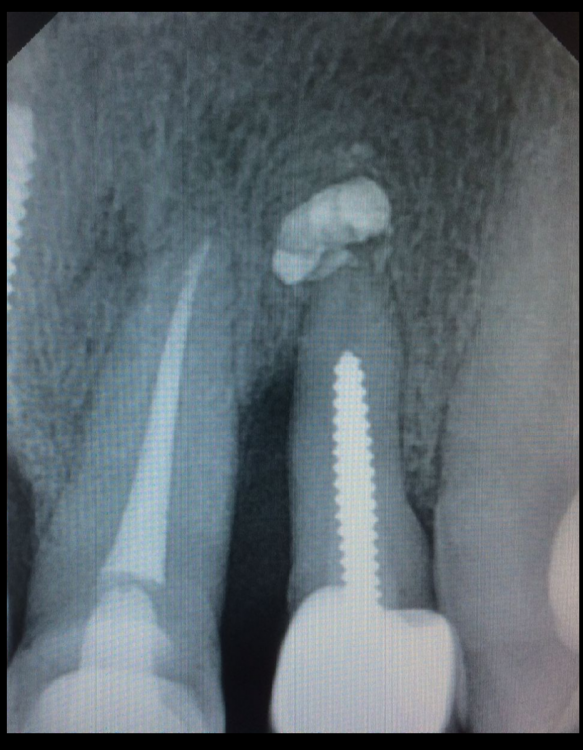

Карен Аванесов Опубликовано 7 декабря, 2021 Автор Поделиться Опубликовано 7 декабря, 2021 (изменено) 2 часа назад, Fin сказал: Вы же сами знаете что проблем быть не должно ? Старт. И гной и пузырь-волдырь и свищ, классика. Это латеральный резец слева. Изменено 7 декабря, 2021 пользователем Карен Аванесов Ссылка на комментарий

Карен Аванесов Опубликовано 7 декабря, 2021 Автор Поделиться Опубликовано 7 декабря, 2021 3 часа назад, Fin сказал: Вы же сами знаете что проблем быть не должно ? Это я давно делал, ну подумал и конечно решил что волнений это не стоит. Больше волновался за центральный резец. Ссылка на комментарий

Fin Опубликовано 7 декабря, 2021 Поделиться Опубликовано 7 декабря, 2021 2 часа назад, Карен Аванесов сказал: Старт. И гной и пузырь-волдырь и свищ, классика. Это латеральный резец слева. Классно, без графта? Формироваетль 5 мм ? Ссылка на комментарий

Карен Аванесов Опубликовано 7 декабря, 2021 Автор Поделиться Опубликовано 7 декабря, 2021 Только что, Fin сказал: Классно, без графта? Формироваетль 5 мм ? здесь без всего, графт очень редко. Ссылка на комментарий

Карен Аванесов Опубликовано 7 декабря, 2021 Автор Поделиться Опубликовано 7 декабря, 2021 Не нравится мне состояние периапикальных тканей у центрального резца, жалоб у пациента нет, но что то не нравится мне. Грешу на то, что он между двумя имплантатами, но, контакты физиологичны, без сдавливания. Ссылка на комментарий

Fin Опубликовано 7 декабря, 2021 Поделиться Опубликовано 7 декабря, 2021 5 минут назад, Карен Аванесов сказал: Не нравится мне состояние периапикальных тканей у центрального резца, жалоб у пациента нет, но что то не нравится мне. Грешу на то, что он между двумя имплантатами, но, контакты физиологичны, без сдавливания. На втором снимке кажется, что уже есть изменения в периодонте резца. Ссылка на комментарий